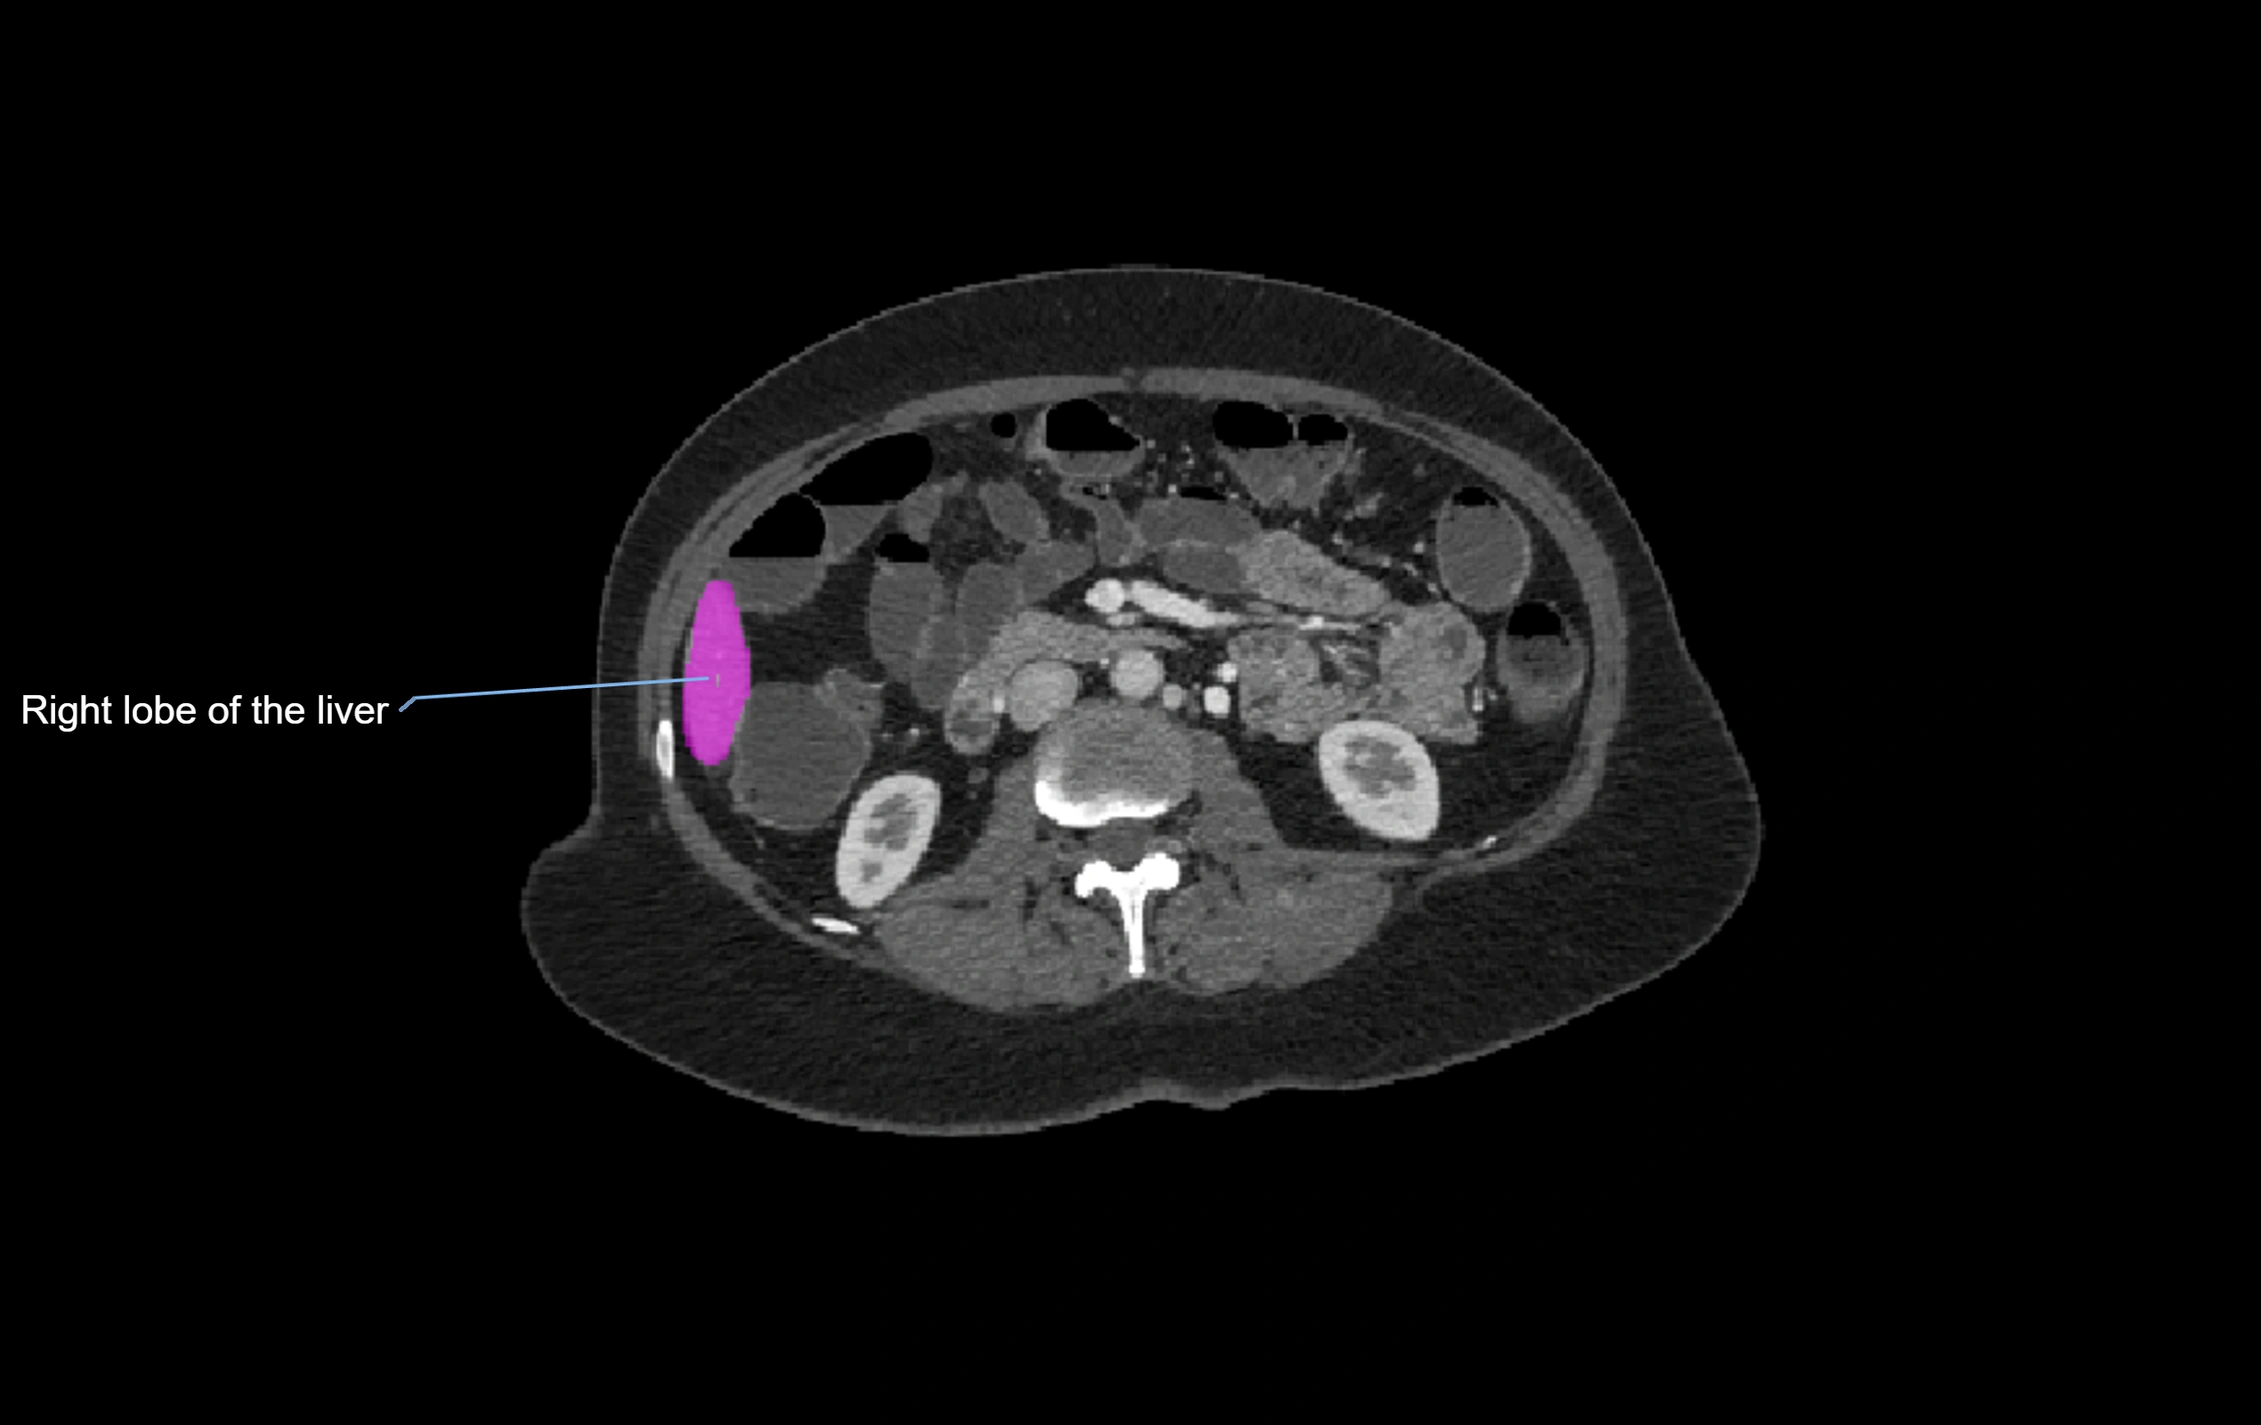

CT Image

image